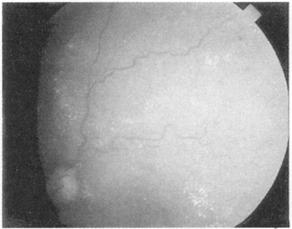

在熟悉之前你需要看一些视网膜图,花时间去注意黄斑,为一淡红色斑点。按顺序描述你的所见为佳,寻找背景,不是乳头或黄斑,而是出血和渗出,检查视网膜血管,注意粗细和规则——小动脉的直径是静脉的2/3,分布规则。正常的视乳头和糖尿病、高血压、乳头水肿和视神经萎缩见图(图151~155)。

图152 糖尿病眼底的改变,可见斑点状出血和渗出

图153 高血压病眼底改变,可见血管屈曲

图154 视神乳头水肿,可见神经盘处模糊

图155 视乳头肥大,可见神经盘变清晰、苍白